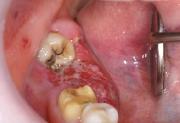

口腔がん

下顎歯肉がん(下あごの歯ぐきのがん)